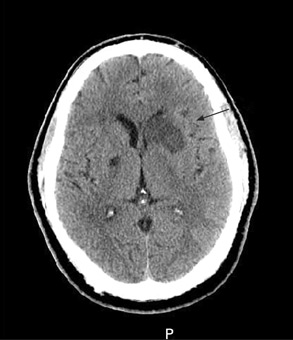

[Figure caption and citation for the preceding image starts]: თავის ტვინის არაკონტრასტული კტ სკანირება ავლენს მარცხენა ბაზალური განგლიის ქვემწვავე იზოლირებულ ინფარქტს მარცხენა ფრონტალური რქის??? მასის ეფექტით.Courtesy of BMJ Case Reports 2009; doi:10.1136/bcr.10.2008.1139 [Citation ends].